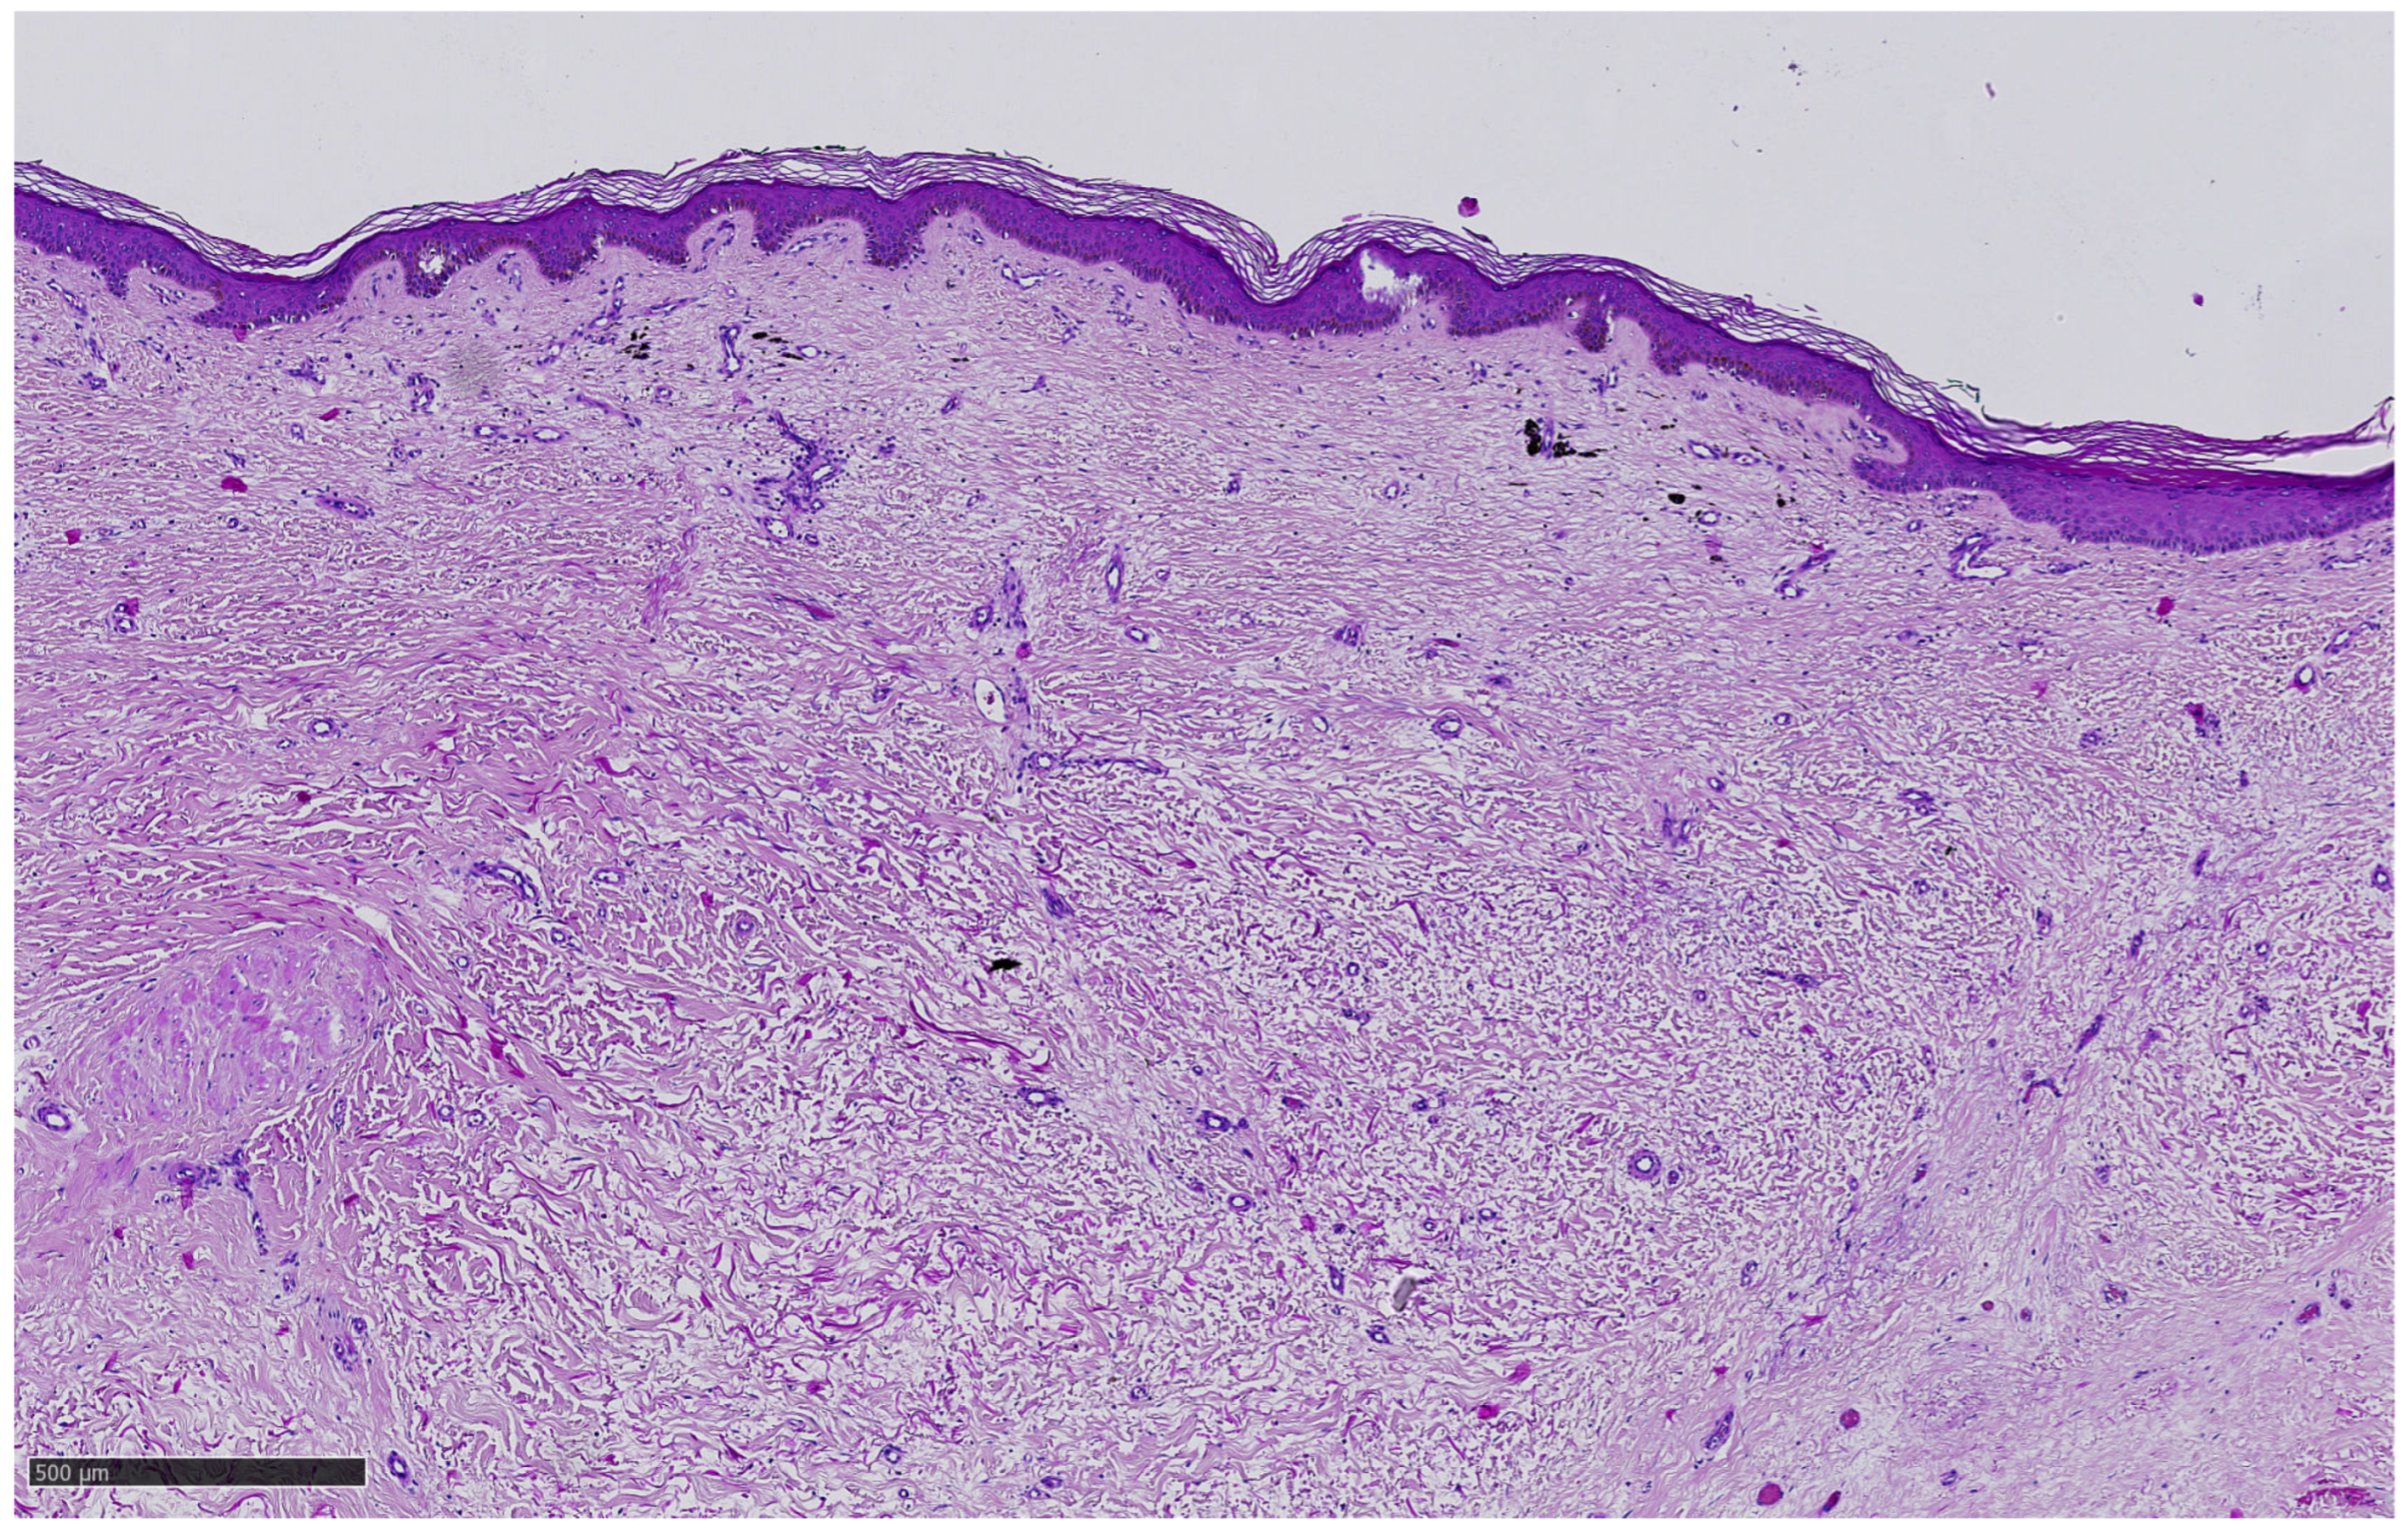

3.2. Histologic and IHC Findings

| TIL | Grade 1 | Grade 1 |

| CD3 | 1 (10%) | 1 (10%) |

| CD4 | 1 (2%) | 1 (2%) |

| CD8 | 1 (15%) | 1 (10%) |

| CD56 | 1 (1%) | 1 (1%) |

| FoxP3 | 1 (1%) | 1 (1%) |

| CD163 | 1 (10%) | 1 (15%) |

| Spatial distribution of CD8 | inflammed | inflammed |